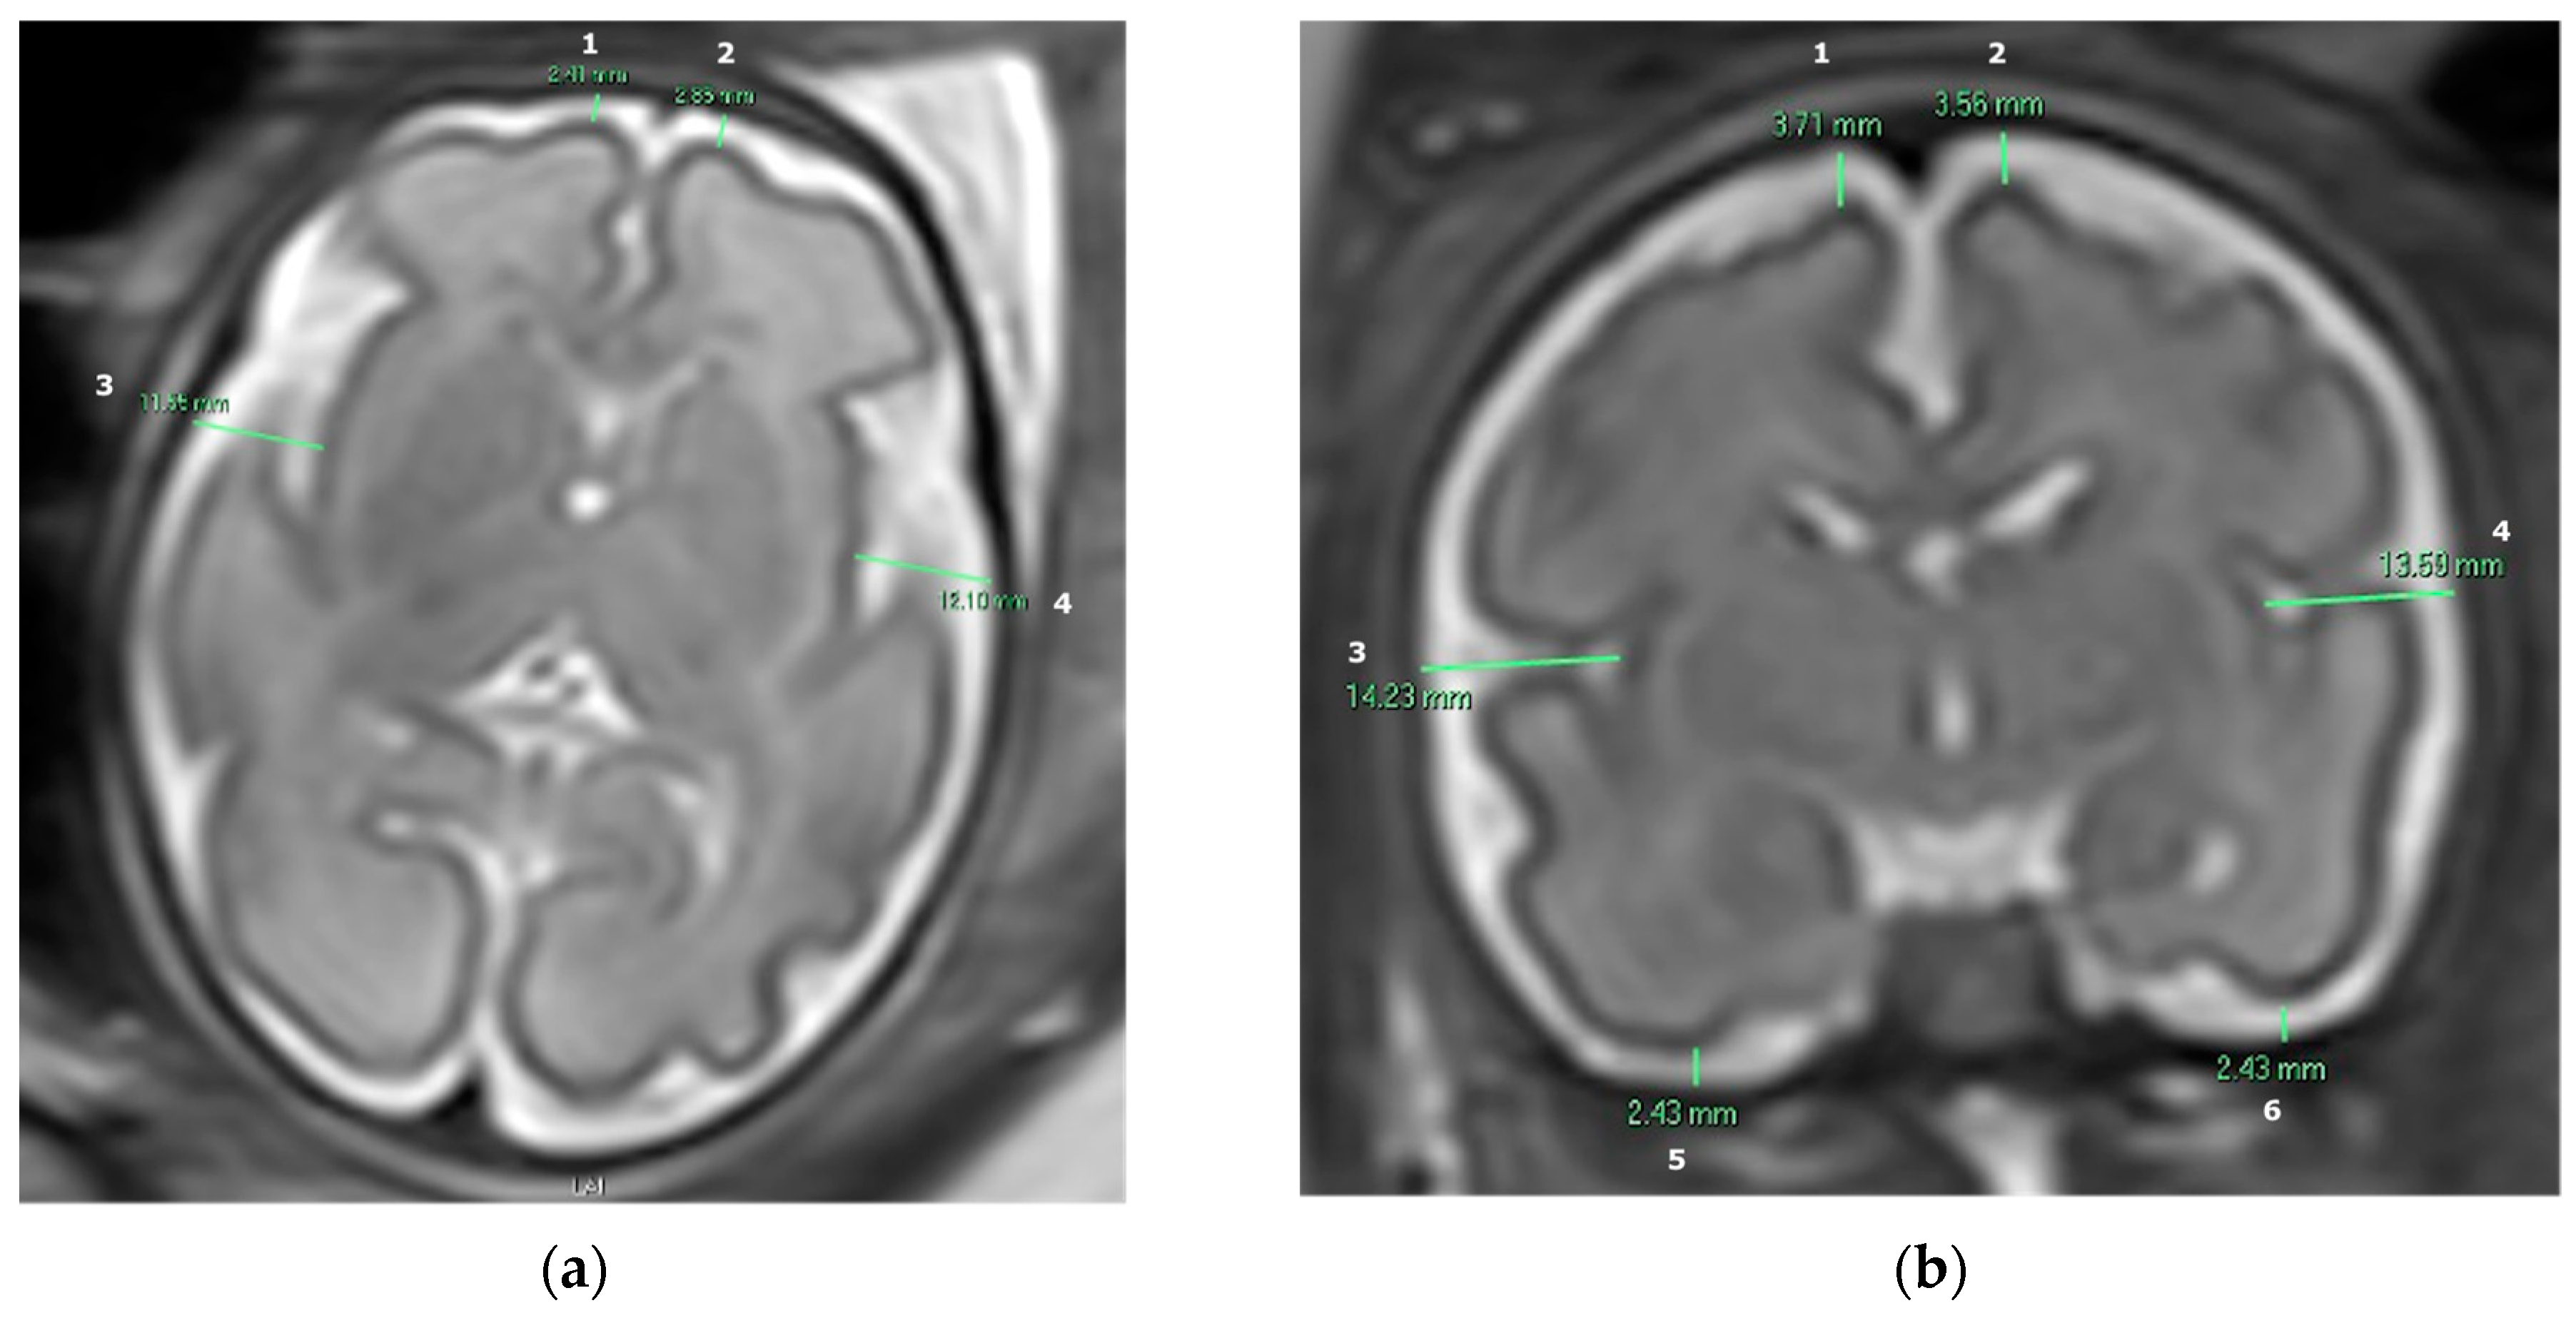

2.3. Subarachnoid Space Width Measurements